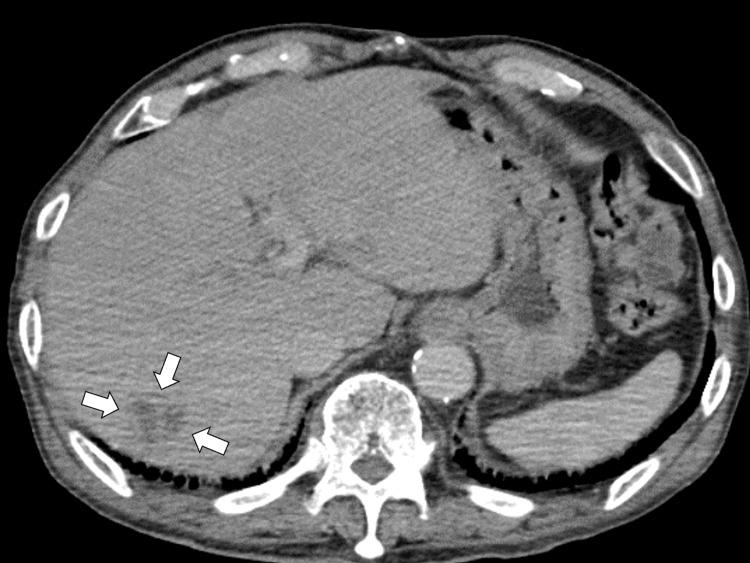

一名患有多种合并症的82岁男性因发热和活动能力下降前往一家乡村医院就诊,被诊断为高毒力肺炎克雷伯菌(HVKP)所致的肝脓肿。最初采用静脉抗生素治疗使影像学表现有所改善,但患者出现复发性菌血症、腰痛,最终发展为硬膜外脓肿、感染性心内膜炎和脑脓毒性栓子。尽管升级了抗生素治疗并给予支持治疗,但其病情仍恶化,由于严重脓毒症和心力衰竭,手术干预被认为不可行。他于住院第27天死亡。该病例凸显了HVKP感染的诊断和治疗挑战,尤其是在患有基础疾病的老年人中。即使早期治疗且原发性脓肿得到明显控制,HVKP仍可经血行播散,导致严重并发症。临床医生应高度怀疑其发生全身播散,并考虑延长治疗时间和加强监测,尤其是在老年或免疫功能低下的患者中。